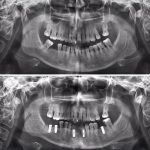

Diş Estetiği ve İmplant (Bölüm 4)

Randevu Oluşturmak İster misiniz?